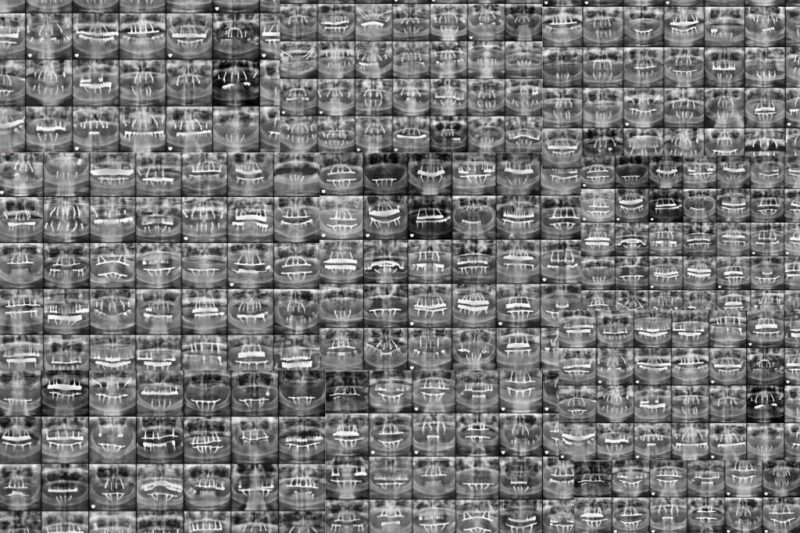

Dental Implants

0

+